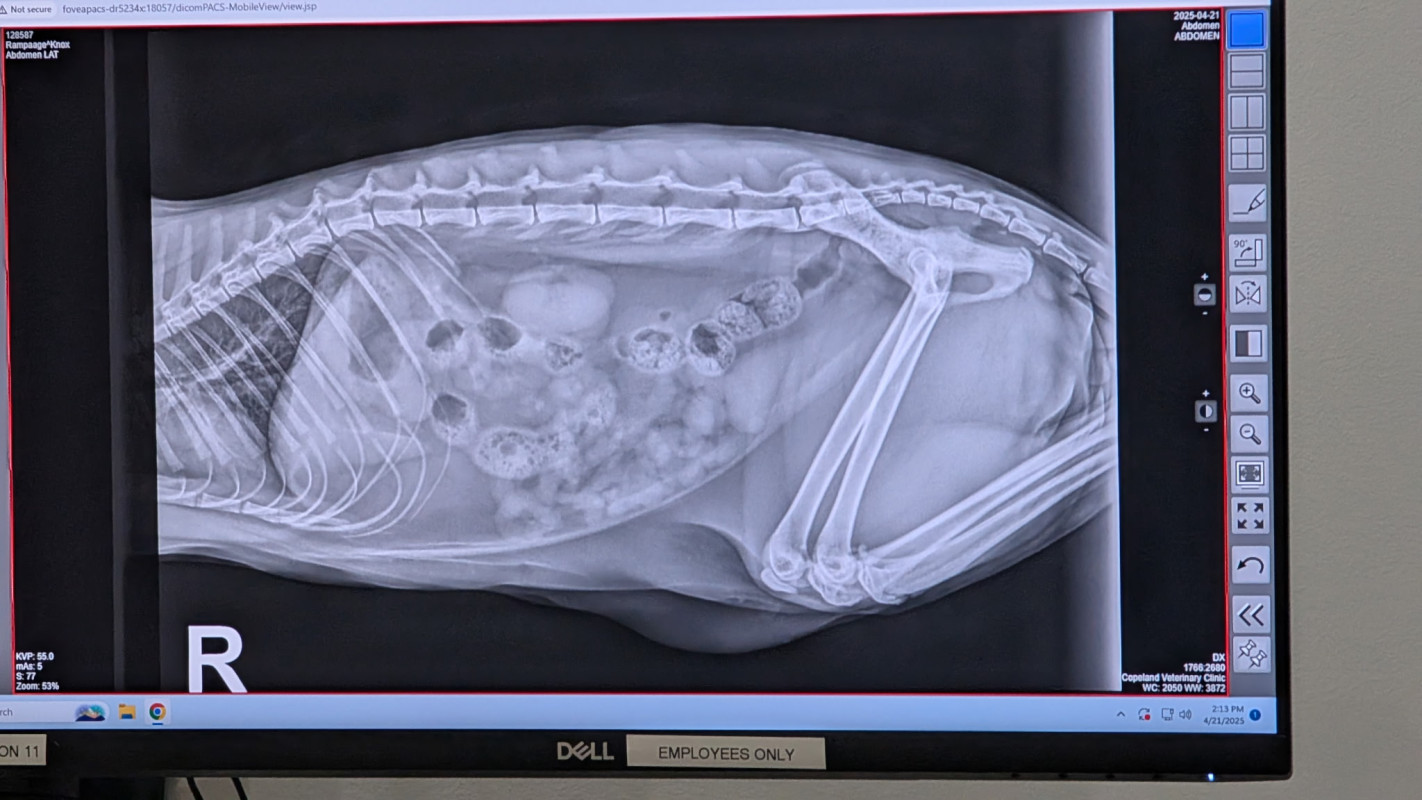

My Daughter’s cats name is Knox he’s her everything, we he got into something and now he has an obstruction, we took him to the vet because he was throwing up a lot and wouldn’t eat anymore (that’s not normal for him) when we brought him in they did an X-ray on him and that’s when they saw the obstruction. They gave him fluids and nausea medicine, and said that if he keeps throwing up and hasn’t passed poop then he’s going to need surgery. We are going in day four of no eating and not wanting to drink. We do give him water in a syringe but he still hasn’t wanted to move around or drink. We were hoping that it was going to pass on its own without surgery but it’s not looking good for him. We are going to have to do surgery.